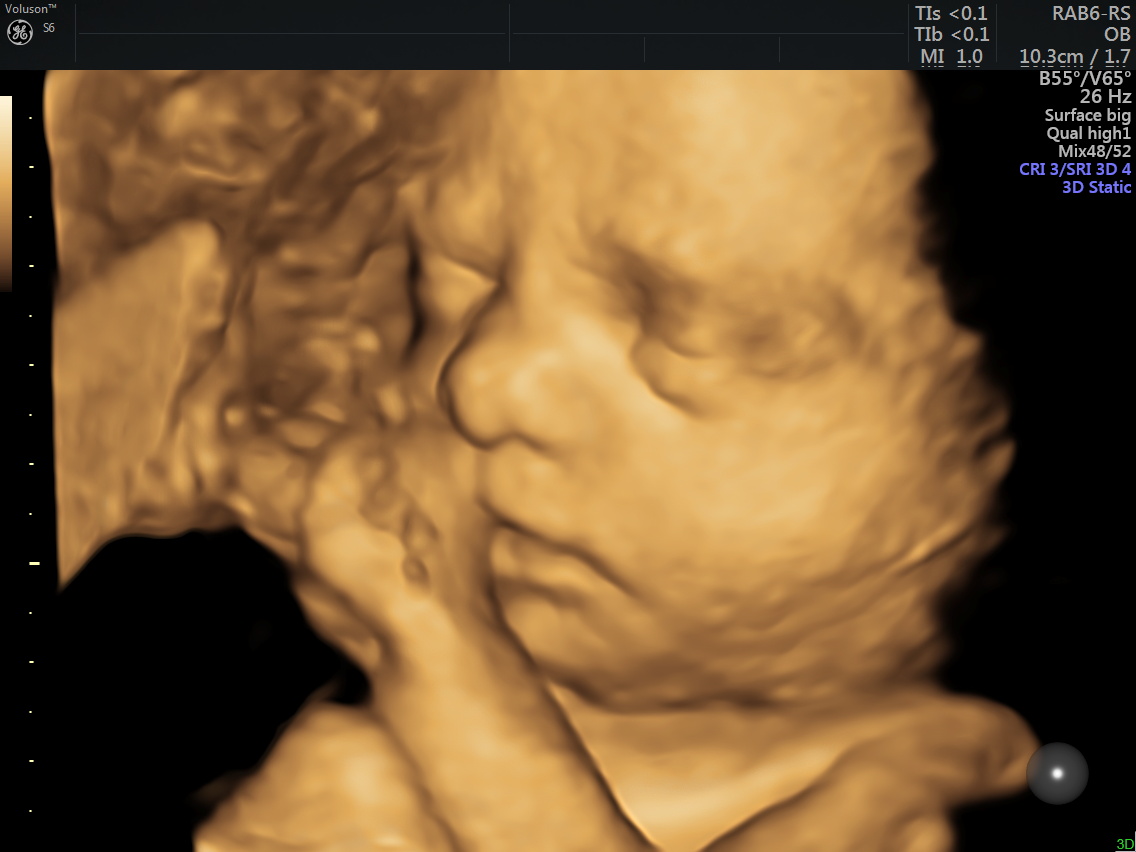

4 Boyutlu Renkli Ultrason

4D (dört boyutlu), Renkli, Ayrıntılı Gebelik Ultrasonu

Anne adayı 4D Renkli Ultrason Sayesinde Bebeğine Daha Kolay Bağlanabilir.

4 boyutlu renkli ultrason cihazı ile çok erken dönemde cinsiyet, yarık dudak, yarık damak, eksik parmak, beyin ve omurilikten kaynaklanan rahatsızlıkların erken tanısı konulabiliyor.